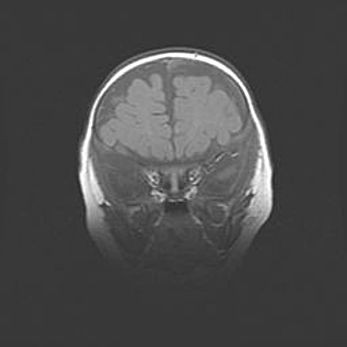

Сообщающаяся гидроцефалия. Кистозная энцефаломаляция головного мозга.

Возраст: 3 месяца 4 дня

Вес: 3100 г

Пол: женский

Окружность головы: 34 см

Срок гестации: 31 неделя

Кистозная энцефаломаляция головного мозга - одна из форм поражения головного мозга в детском возрасте. Характеризуется возникновением множественных и распространённых кист в коре, белом веществе и подкорковых образованиях головного мозга у плодов, новорождённых и детей раннего возраста. Развитие кистозной энцефаломаляции связано с внутриутробной асфиксией и гипотонией, родовой травмой, тромбозом синусов, пороками развития сосудов, инфекциями, сепсисом и другими причинами. Наиболее значимые инфекционные агенты: вирусы простого герпеса, цитомегалии, краснухи, токсоплазмы, энтеробактерии, золотистый стафилококк и другие.